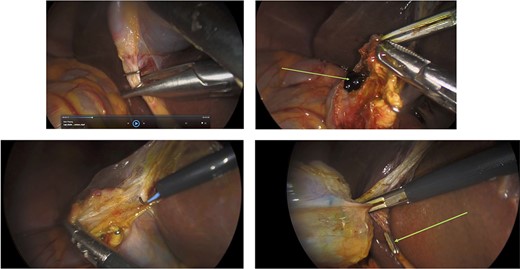

Surgery: laparoscopic cholecystectomy. (a) clipping of the common bile duct. (b) retrograde dissection of the fundus of the gallbladder. (c) iatrogenic gallbladder injury and spillage of pigment stones (green arrow). (d) completion of the retrograde dissection with visualization of the cystic duct stump (green arrow).

An elective gastroscope showed a soft tissue mass on the posterior wall of the body of the stomach (Fig. 2a). This appeared to be an underlying submucosal tumour with no mucosal involvement. Biopsies taken showed a normal mucosa with no malignant or premalignant mucosal pathology. A complete pathological diagnosis could not be ascertained and after an extensive discussion with the patient and her family, conservative management was contemplated rather than a surgical resection. Her symptom profile did not fit clearly with either biliary colic or a gastric GIST. Three months later the patient returned to consider surgery as the pain was not subsiding. She had a second gastroscope to mark the tumour margins with methylene blue as part of her workup for a laparoscopic gastric wedge resection (Fig. 2b). The mucosa over the lesion now showed an ulceration which we ascribed to excessive tumour growth (Fig. 2c). She also requested a concomitant laparoscopic cholecystectomy as we could not clearly elucidate the aetiology behind her abdominal pain. An informed consent was signed along with permission to record the surgical procedure. The laparoscopic cholecystectomy, initially performed, was uneventful. This was a combined antero-retrograde cholecystectomy (Fig. 3a–d). The greater curvature of her stomach was mobilized laparoscopically until the lesion was clearly visualized on the posterior wall with the aid of the methylene blue dye injected at endoscopy (Fig. 4a–c). The decision was then made to convert to open surgery and the lesion excised with a 1 cm margin (Fig. 4d). The gastrotomy wound was closed in two layers with a 2–0 polydioxanone absorbable running suture (Fig. 4e). Her physiological recovery was unremarkable, and she was discharged home on post-operative Day 5. Pathology confirmed the presence of a gastric GIST with clear surgical margins. Gallbladder pathology showed a chronic cholecystitis and pigment stones (Fig. 5).